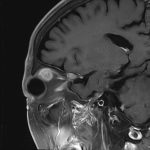

症例 '25年11月

No.

696

※ 画像をクリックすると拡大表示します。症例No.は平成29年から起算しています。

年_番号

手術年月

患者年齢

’25_98

'25年11月

70代

病名

術式

備考

眼窩腫瘍

頭蓋内腫瘍摘出術

断層撮影

手術後